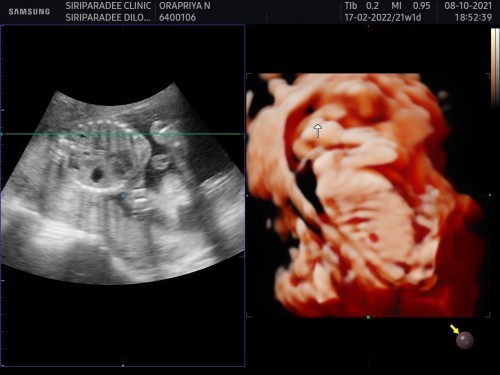

แม่ๆคะ ขอดูใบซาวเพศ ของแม่ๆหน่อยคะ

ตอนนี้21wแล้วยังไม่รู้เพศเลย